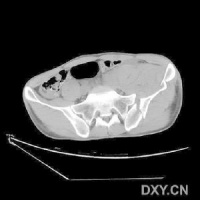

CT检查对骨盆骨折虽不属常规但它可在多个平面上清晰显示骶髂关节及其周围骨折或髋臼骨折的移位情况,因此凡涉及后环和髋臼的骨折应行CT检查骨盆三维重建CT或螺旋CT检查更能从整体显示骨盆损伤后的全貌,对指导骨折治疗颇有助益但应铭记对血流动力学鵻不稳定和多发伤患者,后前位全骨盆X线片是最基本和最重要鵻的放射学检查不要在拍摄特殊X线片上花费时间,更为重要的是尽快复苏。